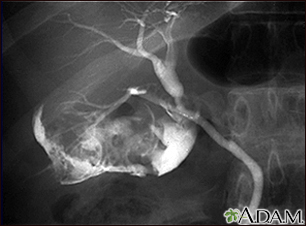

Endoscopic Retrograde Cholangiopancreatography (ERCP)Endoscopic retrograde cholangiopancreatography (ERCP) was once the gold standard for detecting common bile duct stones, particularly because stones can be removed during the procedure. (See Surgery below for details on the procedure.)However, this technique is invasive and carries a risk for complications, including pancreatitis. With the technological advancement of noninvasive imaging techniques, ERCP is now generally limited to patients who have severe cholangitis and a high likelihood of common bile ducts stones, which would need to be removed. It may also be used to diagnose biliary dyskinesia.

- Endoscopic retrograde cholangiopancreatography (ERCP) with endoscopic sphincterotomy (ES) is now the most frequently used procedure for detecting and treating common bile duct stones. The procedure involves the use of an endoscope (a flexible tube containing a miniature camera and other instruments), which is passed down the throat to the bile duct entrance.

A typical ERCP and endoscopic sphincterotomy (ES) procedure includes the following steps:

- The patient is given a sedative and asked to lie on their left side.

- An endoscope (a tube containing fiber optics connected to a camera) is passed through the mouth and stomach and into the duodenum (top part of the small intestine) until it reaches the point where the common bile duct enters. This does not interfere with breathing, but the patient may have a sensation of bloating.

- A thin catheter (tube) is then passed through the endoscope.

- Contrast material (a dye) is injected through the catheter into the opening of the duct. The dye allows x-ray visualization of the biliary tree (the system of ducts through which bile flows, including the common bile duct) and any stones contained in the area.

- Instruments may also be passed through the endoscope to remove any stones that are detected.

- The next phase of the procedure is known as endoscopic sphincterotomy (ES). It is also sometimes referred to as papillotomy, although this is a slightly different variation. ES widens the junction between the common bile duct and intestine (the ampulla of Vater) so that the stones can be extracted more easily. With ES, a tiny incision is usually made in the opening of the common bile duct and through the muscles that enclose the lower common bile duct (the sphincter of Oddi).

- One recent alternative to ES is the use of a small inflatable balloon (a procedure known as endoscopic balloon dilation) that opens up the ampulla of Vater to allow stones to pass. This variation does not involve cutting muscles, and offers a lower risk of bleeding and injury to internal structures. However, this carries a higher risk for pancreatitis.

- Once the junction has been opened, the stones may pass on their own, or they may be extracted with the use of tiny balloons, or sometimes baskets.

- During ERCP, a choledochoscope can be used to directly access the bile duct through the ERCP scope to visualize and potentially disrupt and/or remove stones (Spyglass is a disposable system that has been designed for this use).